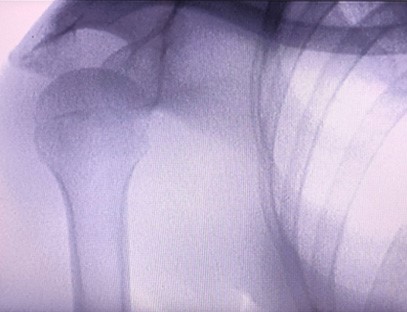

מכשיר רנטגן ניידהוא מינון קרינה נמוך, מכשיר נייד בטוח מאוד שיכול להשיג תמונות באיכות גבוהה תוך הפחתת החשיפה לקרינה. הוא מפצה על החסרונות של ציוד גדול בבית החולים וניתן להזיז אותו ולסחוב אותו בכל עת. מתאים במיוחד ליחידות וליחידים עם תקציב לא מספיק ודרישות נמוכות לתמונות. מכונת הרנטגן מהדור החדש שלנו מצוידת במסך גדול בחדות גבוהה בגודל 10 אינץ', בעל טווח זווית צפייה גדול יותר ויכול לראות באופן מלא דרך כל כף היד, כולל שברים, נקעים, דלקות פרקים וגידולי עצמות. ניתן לחבר אותו למדפסת סרטים להדפסת סרטים אורטופדיים, ויכול לשמש גם לייצור ובדיקות תעשייתיות. אין צורך בחדר חושך, פרספקטיבה ישירה, תצפית בזמן אמת. למכונה זו מערכת הדמיה ברזולוציה גבוהה שיכולה ללכוד תמונות של כל מבנה עצם בצורה ברורה מאוד. לספק את מיטב הציוד והפתרונות לבדיקת קרני רנטגן עבור יצרני מוצרים רפואיים, חיות מחמד, תעשייתיים, אלקטרוניים, מחלקות בדיקה ותחזוקה ומעבדות מחקר.

הִתמַחוּת:מיועד לצרכי מרפאות אורטופדיות, מתאים במיוחד להדמיית רנטגןשל גפיים כגון ידיים, פרקי כף היד, מרפקים, כתפיים, ברכיים, קרסוליים וכו'.

הדמיה ברורה:טכנולוגיית הדמיה דיגיטלית מתקדמת משמשת לספק תמונות רנטגן באיכות גבוהה, המסייעת לרופאים לאבחן במדויק את המצב.